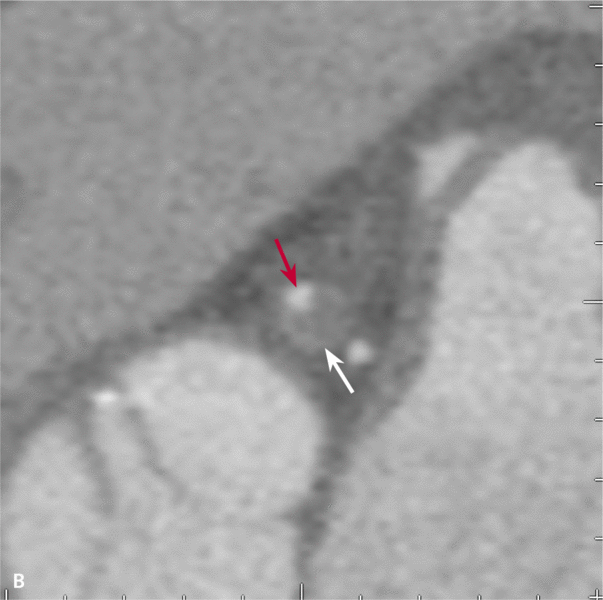

Mężczyzna, lat 68, z niecharakterystycznymi bólami w klatce piersiowej zgłosił się do specjalistycznej przychodni kardiologicznej. W wywiadzie rodzinnym podawał chorobę wieńcową w rodzinie, a osobniczym – nadciśnienie tętnicze i zwiększone stężenie cholesterolu. Wykonana próba wysiłkowa była niediagnostyczna (4,6 MET). Badanie echokardiograficzne nie wykazało istotnych nieprawidłowości. Badanie TK wykonane w trybie ambulatoryjnym uwidoczniło wielopoziomowe zmiany w prawej i lewej tętnicy wieńcowej (ryc. 1A), 50% zwężenie pnia lewej tętnicy wieńcowej z blaszką małej gęstości z remodelingiem dodatnim ściany naczynia (ryc. 1B) oraz niedrożność prawej tętnicy wieńcowej w segmencie 2/3 i wielopoziomowe zmiany w gałęzi diagonalnej i okalającej (ryc. 1C).

RYCINA 1. [A] Rekonstrukcja MIP Inversion. Niedrożność prawej tętnicy wieńcowej. [B] Rekonstrukcja MPR 2D – widoczne światło pnia lewej tętnicy wieńcowej (czerwona strzałka) oraz blaszka o niskiej gęstości powodująca bardzo dużego stopnia remodeling dodatni ściany naczynia (strzałka biała). [C] Rekonstrukcja MPR po krzywej wzdłuż osi długiej prawej tętnicy wieńcowej – wielopoziomowe zmiany niskiej gęstości z niedrożnością segmentu 2.